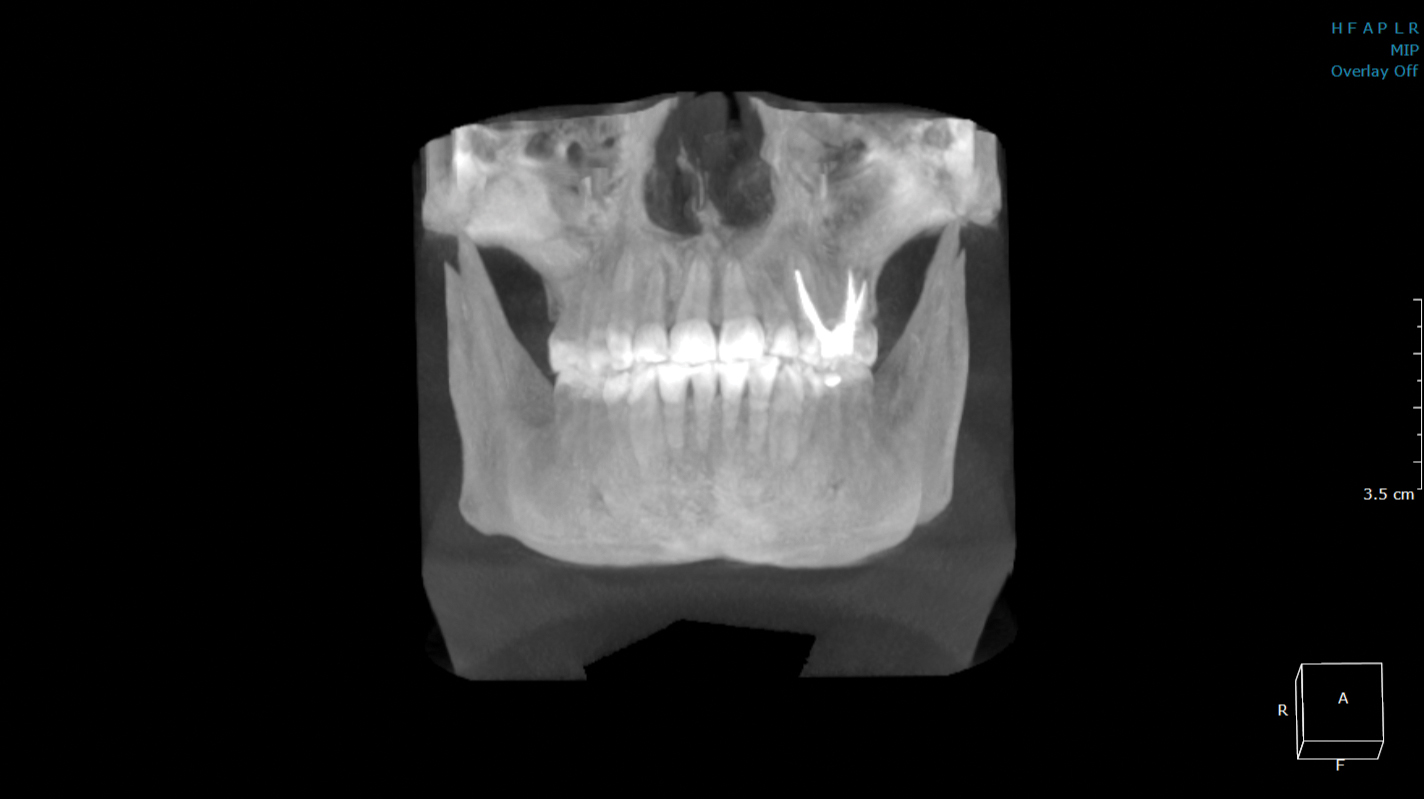

当院には正確で安全な治療を行うための検査機器をとして、最新鋭の歯科用CTシステムを導入しております。このシステムは、低い被ばく線量(総合病院などの医科用CTの1/10以下)で、3次元データの情報を得ることができ、これまでのレントゲン検査の診断が難しかった部分の診断も行えます。これにより患者さんのへのわかりやすい説明と更なる治療成績の向上が見込めます。